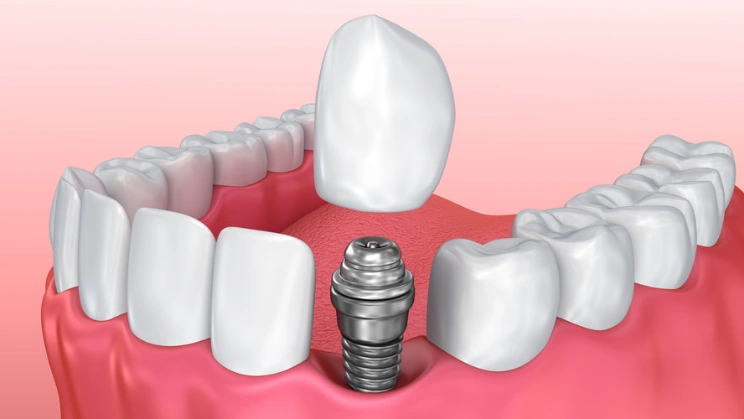

Corona sobre Implantes de Zirconio Fresado CAD/CAM

Las coronas sobre implantes de zirconio fresadas con tecnología CAD/CAM que ofrecemos en Sr Lab Dental son la elección perfecta para restauraciones duraderas y estéticamente agradables. Diseñadas para integrarse perfectamente con los implantes, estas coronas proporcionan una solución duradera y natural.

Calidad y Beneficios:

- Máxima Durabilidad: El zirconio es extremadamente resistente, ideal para soportar la fuerza masticatoria.

- Estética Superior: Proporciona una apariencia natural y homogénea.

- Ajuste Perfecto: La precisión CAD/CAM garantiza un ajuste impecable con los implantes.

- Biocompatibilidad: Material seguro y bien tolerado por los tejidos.

Confía en Sr Lab Dental para una corona sobre implantes que combina durabilidad y estética. ¡Consulta con nuestros expertos hoy!

Corona sobre Implantes de Disilicato de Litio Fresado CAD/CAM

En Sr Lab Dental, nuestras coronas sobre implantes de disilicato de litio fresadas con CAD/CAM ofrecen una solución estética y duradera para tus necesidades dentales. Diseñadas para integrarse perfectamente con los implantes, estas coronas proporcionan una restauración de alta calidad.

Calidad y Beneficios:

- Estética Superior: Su translucidez y color se asemejan al diente natural.

- Durabilidad Confiable: Resistente y duradero para uso prolongado.

- Ajuste Perfecto: La tecnología CAD/CAM garantiza una colocación precisa.

- Biocompatibilidad: Seguro y compatible con los tejidos bucales.

Opta por nuestras coronas sobre implantes de disilicato de litio para una solución estética y funcional. ¡Agenda tu cita en Sr Lab Dental!